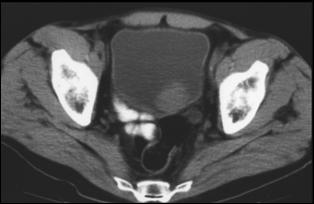

4.3. Tomografia computerizata si rezonanta magnetica nucleara

Informatiile furnizate de aceste metode moderne imagistice ridica procentajul acuratetei diagnostice pana la 85% in aprecierea infiltratiei parietovezicale a tumorilor (T) si la circa 90% pentru decelarea adenopatiei pelviene.

Figura 37. Aspect

tomografic de tumora vezicala. Formatiune tumorala

exofitica protruziva intravezical situata pe peretele

postero-lateral stang. Figura 38. CT pelvin - Tumora voluminoasa in hemivezica